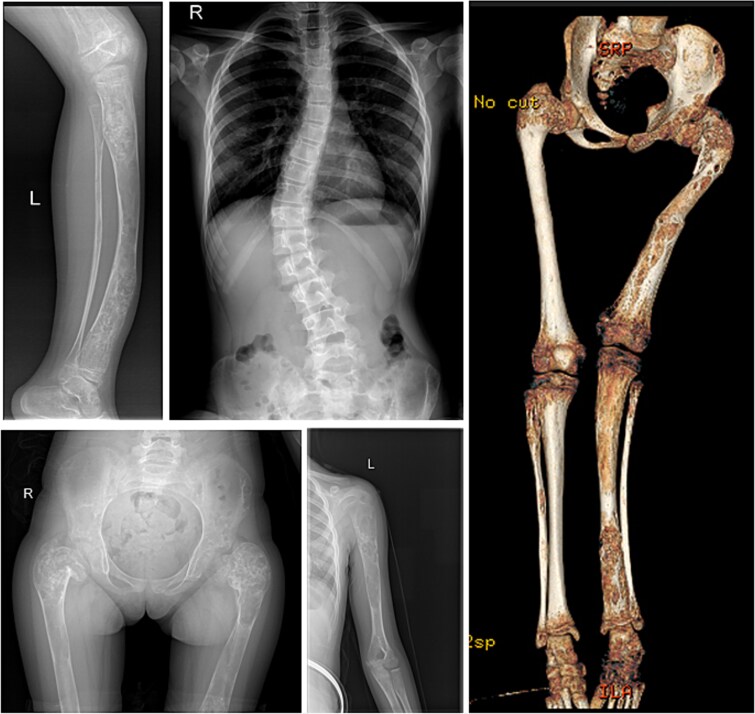

Fibrous dysplasia/McCune-Albright syndrome (FD/MAS) is a rare condition caused by a mutation in the GNAS locus. Apart from endocrinopathies, some cases are characterized by excessive fibroblast growth factor 23 (FGF23) production from abnormal fibro-osseous tissue in FD lesions, resulting in increased renal phosphate excretion. We present a girl with FD/MAS and severe skeletal burden, evidenced by the presence of polyostotic fibrous dysplasia, which was complicated with bone fractures. She also had hyperthyroidism and GnRH-independent precocious puberty. She received zoledronic acid infusions in preparation for hip surgery. Despite optimal conventional management with oral phosphate and alphacalcidol, which was poorly tolerated, she presented persistent hypophosphatemia. To control hypophosphatemia and its deleterious effects on bone health, treatment with burosumab off-label at a dose of 0.66 mg/kg (20 mg) every 2 wk was initiated. Serum phosphate levels normalized within 2 wk of treatment. Laboratory results showed improvement in serum alkaline phosphatase (ALP) and PTH levels. After the second injection of burosumab, phosphate and PTH rose above the normal range with normal vitamin D levels; therefore, the interval between doses was increased to 3 wk, and calcium 500 mg daily was added. However, phosphate levels dropped again below normal range, so she had to return to 2-weekly injections of 20 mg. After 11 mo on burosumab, she remains with high normal phosphate levels and normal PTH and ALP values. Burosumab is well tolerated, with no adverse events to date. Burosumab is a human monoclonal antibody against FGF23 that reduces the risk of developing FGF23-mediated hypophosphatemia and its associated complications. Burosumab should be considered as an effective and safe alternative strategy for FGF23-mediated hypophosphatemia in FD/MAS for those who either cannot tolerate or do not respond to conventional therapy. To our knowledge, this is the fourth published case worldwide describing successful treatment with burosumab in FD/MAS.